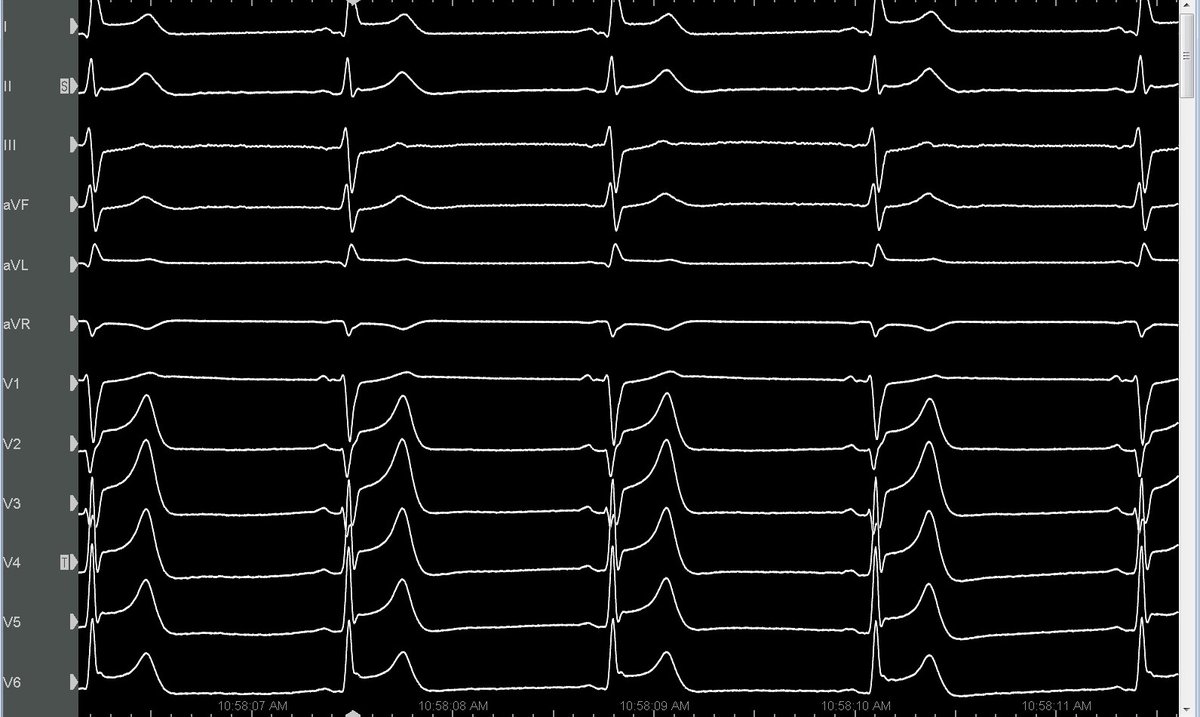

Ethanol VT ablation a challenging case from our lab Refrerered for Recured VT after ablations, 1st anteroseptal VT Optrell, revealing a complete intramural circuit. Ethanol infusion → terminated the first VT. 2nd inferoseptal: Ethanol into MCV septal branch terminated VT

Our Ethanol Ablation for VT series! Non-ischemic CMP No endo scar, septal reentry w/ focal endo-epi activation 💡 Intramural circuit suspected ⛔️ Long endo RF → transient VT stop 🎯 Best precocity at AIV septal branch os endo neighbor Ethanol injection VT termination #Epeeps